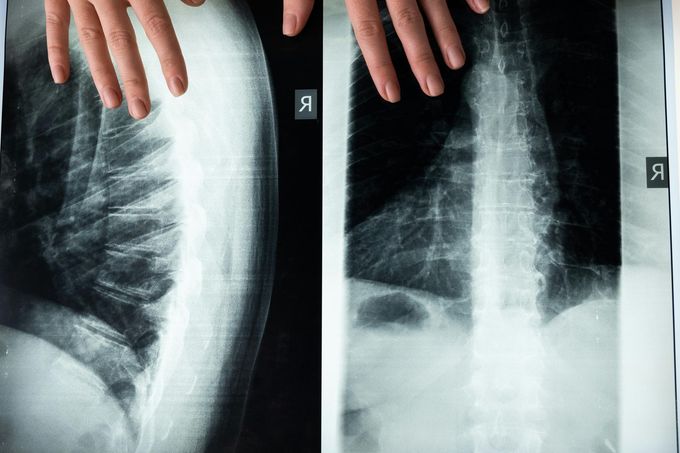

Röntgen- und Ultraschalldiagnostik des Stütz- und Bewegungsapparates

Bildgebende Verfahren zur präzisen Diagnose von Erkrankungen an Knochen, Gelenken und Weichteilen.